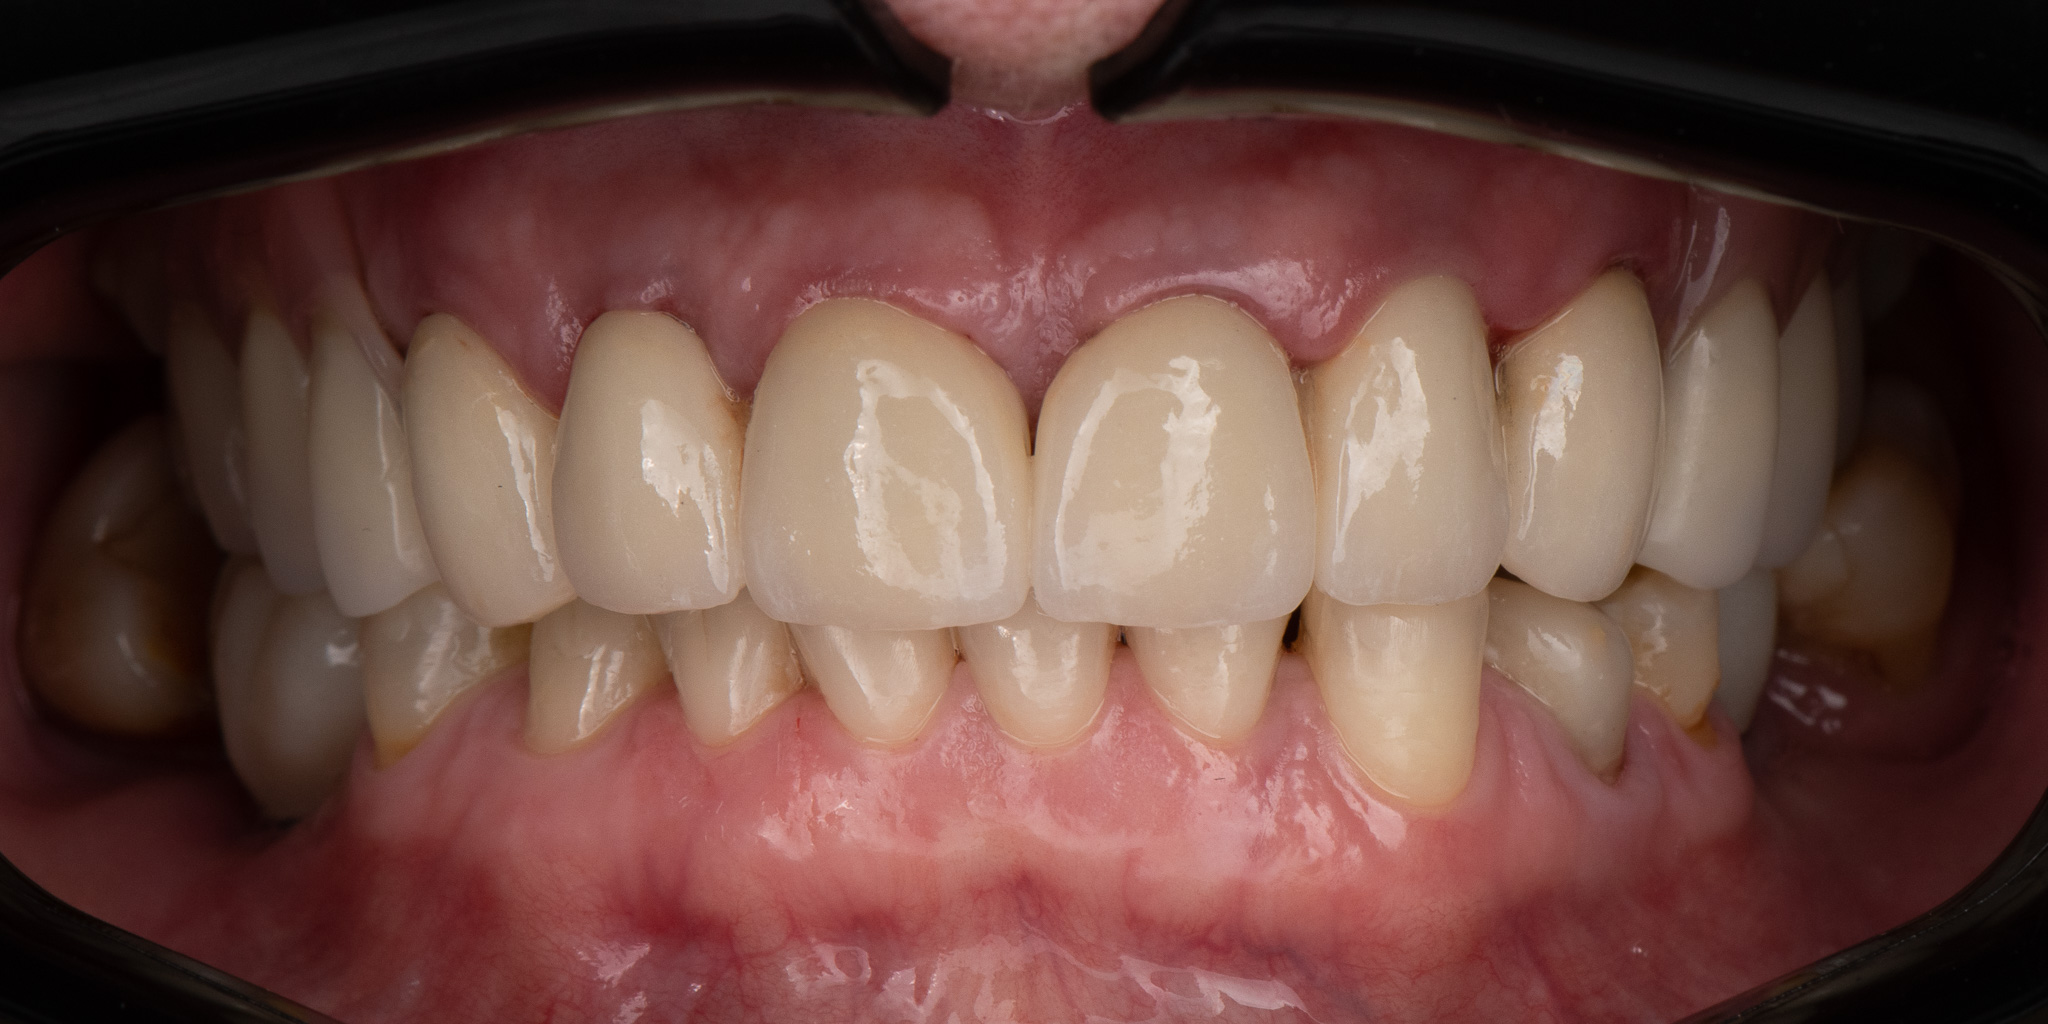

Pacjent 3

Pacjent zgłosił się ze zużytym tymczasowym mostem protetycznym

Zaplanowane leczenie obejmowało wykonanie nowych koron ceramicznych na podbudowie metalowej oraz protez szkieletowych górnej i dolnej.